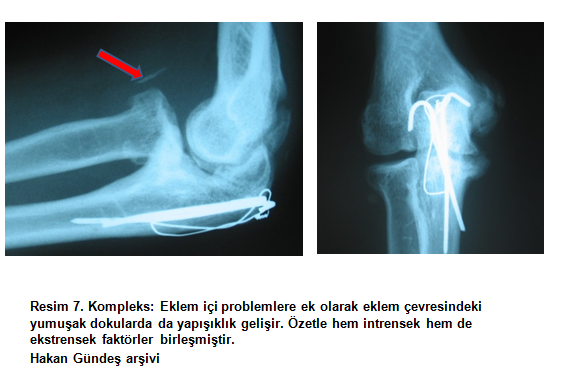

3)Kompleks: Başlangıçta intrensek etkenlerle başlayan kısıtlılıkta ekstrensek faktörlerin ikincil olarak baskın olması durumu (sekonder ekstrensek). Yani eklem içi problemler nedeni ile oluşan ağrı, eklem hareketsiz tutularak tedavi edilmeye çalışılır ve buna bağlı olarak eklem çevresindeki yumuşak dokularda yapışıklık gelişir. Özetle hem intrensek hem de ekstrensek faktörler birleşmiştir (resim 7.